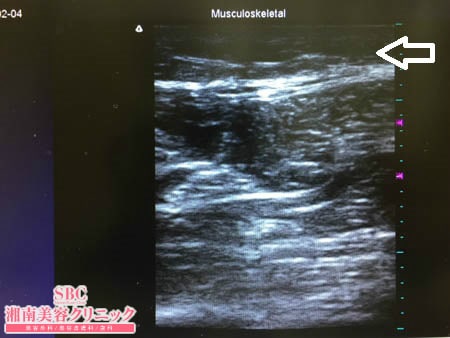

No.185723【脂肪吸引】【動画あり】湘南美容外科全ドクターの脂肪吸引最高責任者である竹田先生による脂肪吸引のフォトギャラリー! 他院の再手術!10年ぐらい運動し続けても細くならない太ももを細くする! 術中3Dタッチビュー・左太もも後面

いつものように3Dタッチビュー(超音波)で

皮下脂肪層を評価してみましょう。

画像が示すように